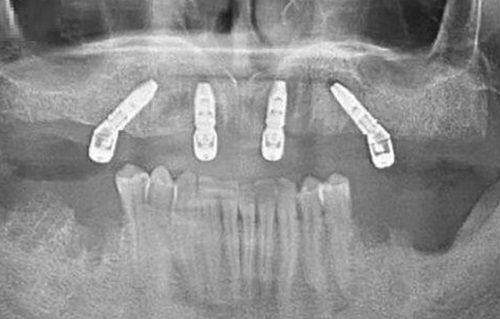

3. 无牙颌种植:无牙颌患者的口腔情况较为复杂,牛言海医生凭借丰富的经验和不错的技术,能够为无牙颌患者提供有效的种植解决方案。他采用精良的All - on - 4等种植技术,只需植入少量种植体就能支撑全口牙桥,大大缩短了治疗时间,提高了患者的生活质量。

1. 精细种植技术:牛言海医生运用精良的数字化设备和技术,如三维CT扫描和数字化导板设计,能够严谨地确定种植体的位置和角度,避免损伤周围的神经和血管,提高种植的成功几率和安心性。